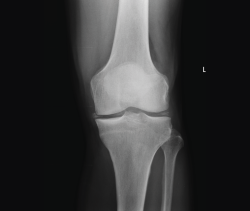

3. Artrosis

La gonartrosis es la causa más frecuente del dolor de rodilla después de los 50 años. En la radiografía se observa una reducción de la interlínea femorotibial o femoropatelar, y una osteofitosis marginal (Figura 6).

Figura 6. Radiografías anteroposterior y lateral de rodilla: osteofitos en compartimentos femorotibial y femoropatelar.